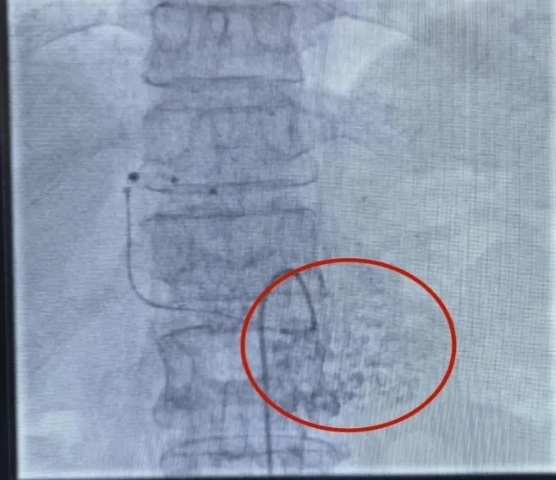

该医院在治疗患者肝脏多发病变过程中,采纳了DSA技术辅助的精确手术方法。手术于20XX年X月X日实施,患者接受了局部麻醉,并通过股动脉穿刺成功置入导管。导管尖端精准定位至肝总动脉。随后,运用高压注射器进行造影,清晰显现了肝左叶病灶的供血动脉路径。继而,将微导管送入肝左动脉,并注入了含碘化油的乳化剂。

手术过程中观察到,碘化油在肝脏左侧病变区域显著聚集,显示出药物在此区域的滞留效果显著。为此,术中采取了分次缓慢注射的方法,以提升疗效并降低潜在副作用。此技术能精确阻断肿瘤血供,最终实现病灶消融。

术后患者恢复状况优良,依据20XX年X月X日的病历记录,未见严重并发症。目前,医疗单位正依据患者术后恢复状况制定后续治疗方案。此情况亦证实了该治疗方法的安妥性与实效性。